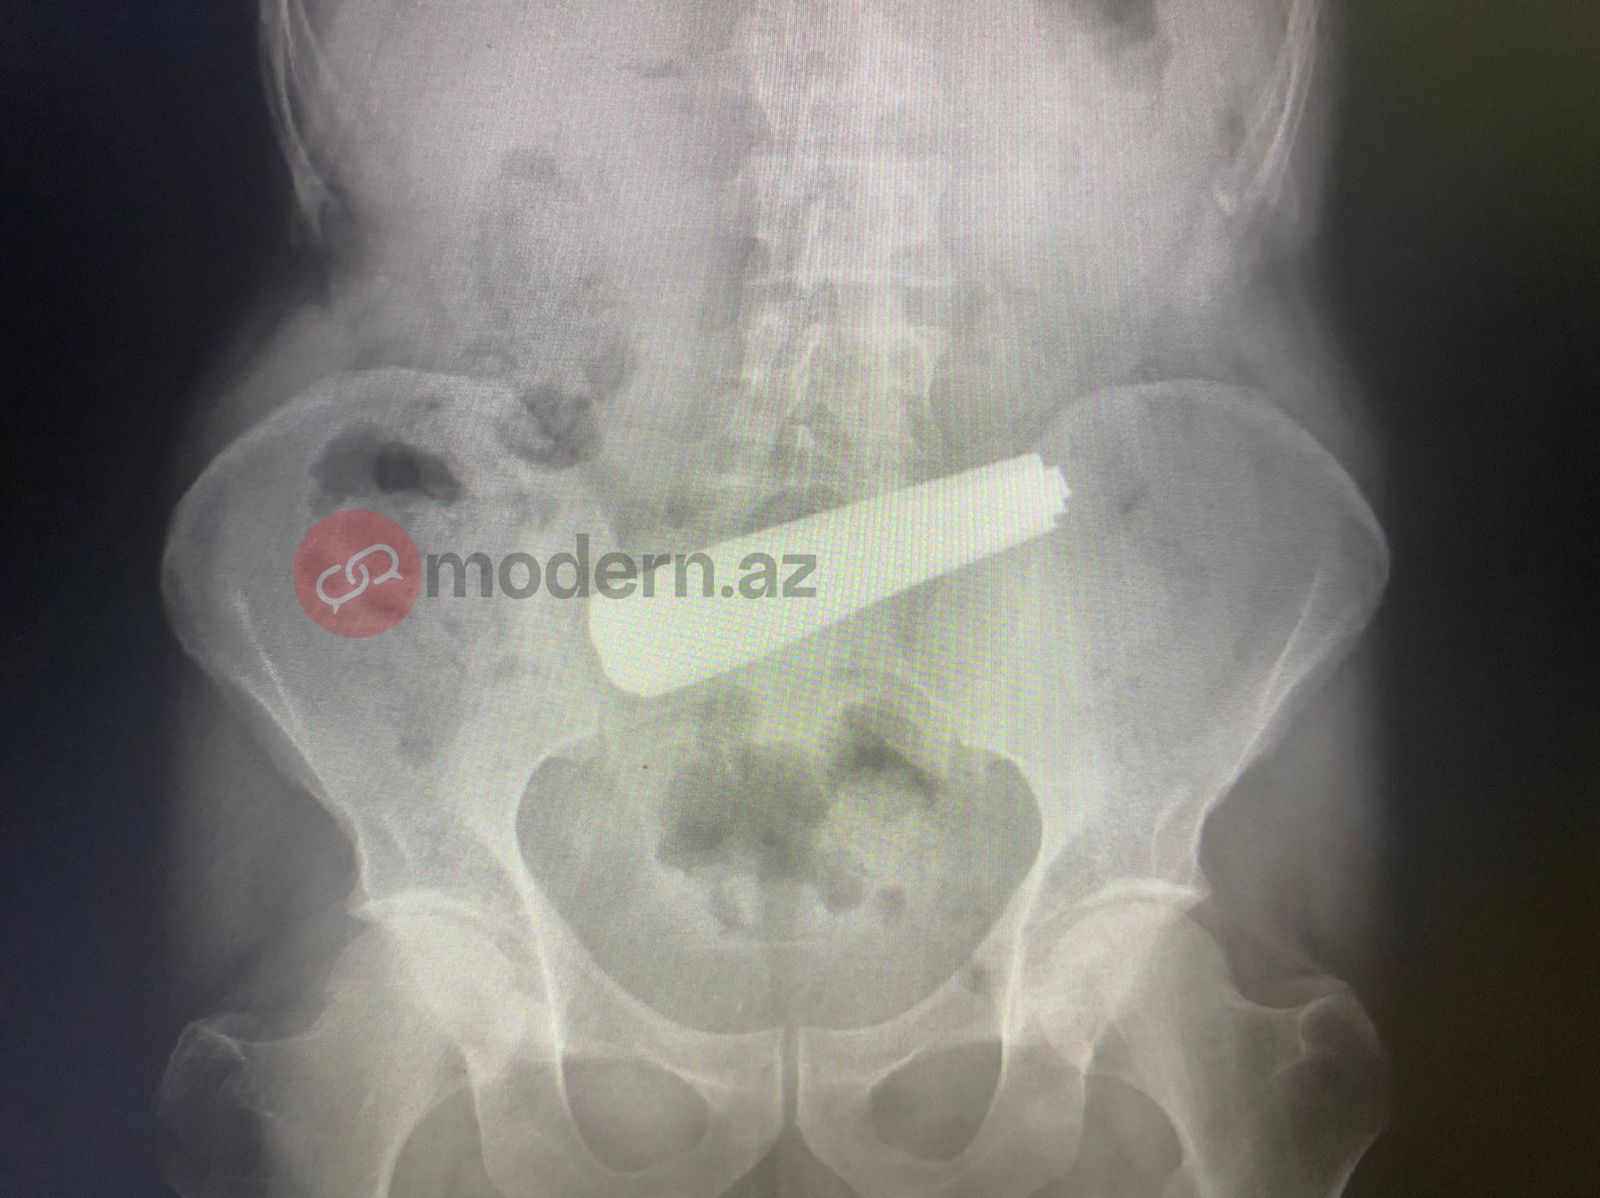

Житель Баку проглотил 9 ложек.

Как передает "Qafqazinfo" со ссылкой на Modern.az, минувшей ночью он был доставлен в Бакинский оздоровительный центр.

В ответ на запрос “Qafqazinfo” в Бакинском оздоровительном центре заявили, что эндоскопическое вмешательство длилось 4 часа, в результате состояние 55-летнего мужчины стабилизировалось.

Было отмечено, что действия пациента, вероятно, были связаны с его психическим состоянием, ситуация требовала срочного медицинского вмешательства.